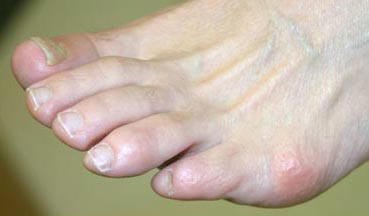

If the joint that connects your big toe to your foot has a swollen, sore bump, you may have a bunion. More than half the women in America have bunions, a common deformity often blamed on wearing tight, narrow shoes, and high heels. Bunions may occur in families, but many are from wearing tight shoes. Nine out of ten bunions happen to women. Nine out of ten women wear shoes that are too small. Too-tight shoes can also cause other disabling foot problems like corns, calluses and hammertoes.

With a bunion, the base of your big toe (metatarsophalangeal joint) gets larger and sticks out. The skin over it may be red and tender. Wearing any type of shoe may be painful. This joint flexes with every step you take. The bigger your bunion gets, the more it hurts to walk. Bursitis may set in. Your big toe may angle toward your second toe, or even move all the way under it. The skin on the bottom of your foot may become thicker and painful. Pressure from your big toe may force your second toe out of alignment, sometimes overlapping your third toe. An advanced bunion may make your foot look grotesque. If your bunion gets too severe, it may be difficult to walk. Your pain may become chronic and you may develop arthritis.

Typical Bunion |